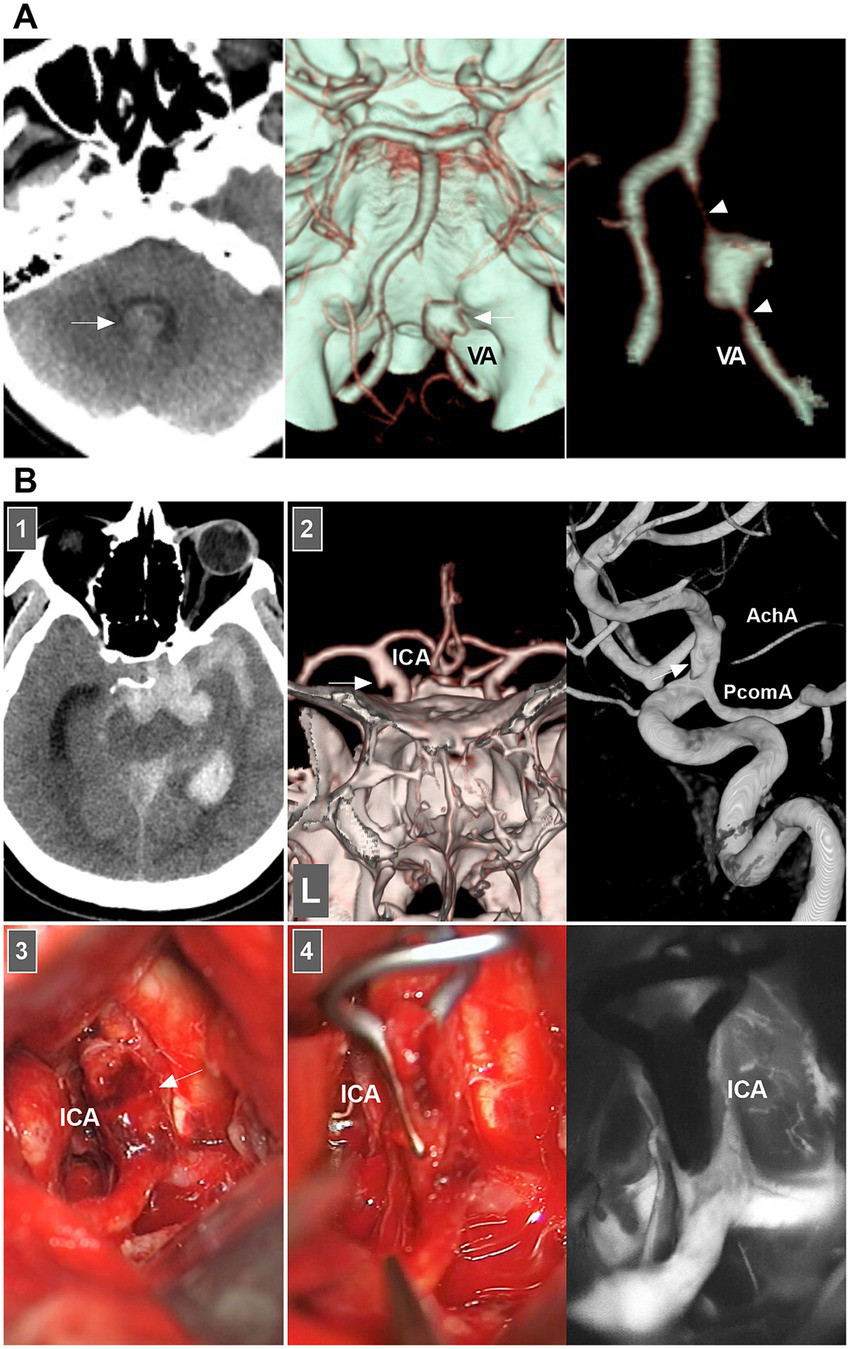

When both the entry and exit can be visualized via angiography, a double lumen is considered (1). When IADs extend inward with no exit on angiography, narrowing or occlusion of the vessel should be considered. When the media penetrates the subadventitia on angiography, aneurysmal dilatation of the outer wall of the vessel should be considered. When the adventitia has penetrated, SAH is likely (Figure 2A) (20–22).

Figure 2

IAD appearance on angiography and open surgery. (A) Left panel: CT showing the hemorrhage in the fourth ventricle (arrow). Middle and right panels: CT images showing a typical VA dissection (arrow in middle panel) presenting with dilatation with stenosis (arrowheads in right panel). (B) Panel 1: CT showing subarachnoid hemorrhage into temporal horn of lateral ventricle. Panel 2: CTA (left panel) and DSA (right panel) images showing a protrusion (arrows) on the left supraclinoid ICA above the PcomA and opposite to the AchA, indicating that the lesion was a dissection or blood blister-like aneurysm. Panel 3: Intraoperative image showing that supraclinoid ICA had subadventitia hemorrhage (arrow), confirming to the dissection not a blood blister-like aneurysm. Panel 4: Intraoperative image (left panel) showing the clipping was performed, intraoperative fluoroscopy (right panel) showing that intracranial ICA was patent. AchA, anterior choroidal artery; CT, computed tomography; CTA, CT angiography; DSA, digital subtraction angiography; IAD, intracranial arterial dissection; ICA, internal carotid artery; PcomA, posterior communicating artery; VA, vertebral artery.

Therefore, according to the European Stroke Organization (ESO) guidelines and a review in Lancet Neurology (2015), IADs are confirmed on the basis of at least one of the following: (a) angiography reveals stenosis or occlusion of an intracranial artery secondarily developing toward a fusiform or irregular aneurysmal dilation at a nonbranching site; (b) angiography revealing an intramural hematoma, intimal flap, or double lumen; and (c) pathological examination confirming the IAD (Figure 2B) (1, 7).